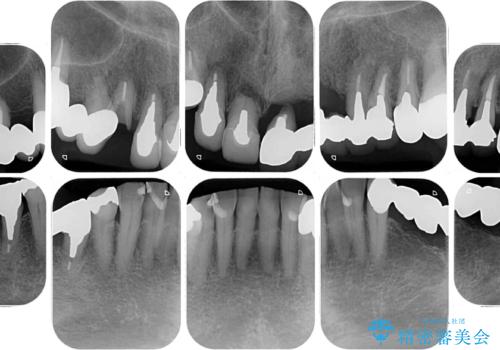

- 抜歯の必要な前歯や、以前治療した前歯のクラウンの外観を気にして来院された患者様です。

上顎犬歯や下顎大臼歯は、必要なところはインプラントを埋入することとしました。

クラウンが不適合であったり、根管治療の必要なほどの痛みのある歯であったり、見た目の気になる前歯などをオールセラミッククラウンに補綴治療を行うこととしました。